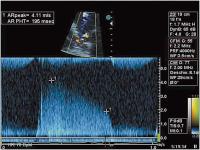

Abbildung 4: CW-Dopplersignal der aortalen Regurgitation mit kurzer Druckhalbwertszeit